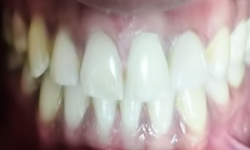

(15) Bleaching Teeth/Teeth Whitening

Before Treatment

After Treatment

Patient Reported to the clinic with a chief complaint of yellow teeth. Teeth Whitening was performed and 2 shade whiter results were achieved.